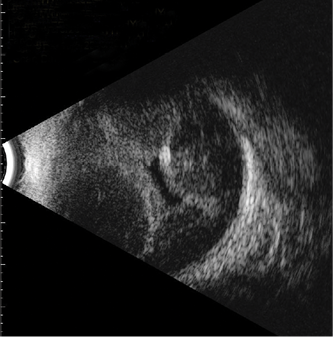

Choroidals can be visualized clinically on fundus examination, where they appear as up to four smooth and dome-shaped (convex) lobes of choroidal elevation with fluid accumulation. Ultrasonography can also be useful, especially in eyes with miotic pupils or other media opacities. B-scan ultrasonography can help to distinguish serous from hemorrhagic choroidals.2 With serous choroidals, B-scan ultrasonography shows dome-shaped retinal elevation with echolucent (dark) subretinal fluid (Figure 1). The retina does not move on dynamic ultrasonography, unlike with a retinal detachment. In severe cases, central retinal apposition—or kissing choroidals—can be seen (Figure 2).

Figure 1. Fundus photography showing a dome-shaped choroidal that occurred in a patient with hypotony after trabeculectomy (A). B-scan ultrasound of the same patient showing moderate echolucent (dark) choroidals due to serous choroidal effusion (B).